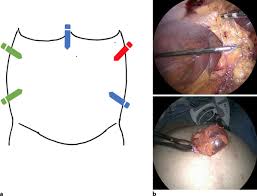

Palmer has performed over 7,000 minimally invasive surgical procedures that reduce pain, enable faster recovery and help patients regain their mobility. If you need any cosmetic, or plastic surgery, dr. May 17, 2020 i felt very at ease. Five of them were found to have extensive periumbilical adhesions. Based in fort lauderdale, palmer cosmetic surgery services the south florida area's cosmetic needs. Palmer has been practicing general ophthalmology and corneal specialization as well as performing cosmetic surgeries since 2009. The left upper quadrant or palmer's point was developed by raoul palmer who advocated the insertion of the veress needle at a range of 3 cm below the left subcostal in the midclavicular line (fig. When umbilical entry is contraindicated we use the left upper quadrant or palmer's point. He has taken care of me, and several of my friends, and we all look fantastic! The hip & knee center is led by renowned surgeon, dr. 19 this technique should be considered for patients with previous laparotomy or obesity, and for exceptionally thin patients. By doing this, one is allowed a visual inspection of the umbilicus and ensuing adhesiolysis to allow subsequent insertion of an umbilical port under direct vision. We take you step by step through this technique to help avoid bowel.

Five of them were found to have extensive periumbilical adhesions. We take you step by step through this technique to help avoid bowel injury. In 1974, palmer first described an abdominal entry point for patients with prior surgery located 3 cm below the left costal margin in the midclavicular line. Based in fort lauderdale, palmer cosmetic surgery services the south florida area's cosmetic needs. Palmer's point can be used in patients with suspected periumbilical adhesions, a history of an umbilical hernia, or multiple failed attempts of insufflations at the umbilicus. The veress needle is introduced through left hypochondria, i.e. While the initial tests showed no signs of cancer, subsequent rises in his psa warranted a second look. Palmer's phone number, address, insurance information, hospital affiliations and more. This entry point, now known as palmer's. Some people claim that they have undergone plastic surgery to get such great bodies. The two majorreasons forchoosing palmer's point inour population were a history of previous open abdominal surgery and the presence of a large uterine or pelvic mass that accounted for 46% and 31% of our cases, respectively. Palmer was very thorough, and exhibited significant expertise. The hip & knee center is led by renowned surgeon, dr.

Principles Of Laparoscopic Surgery Sciencedirect from ars.els-cdn.com Palmer's point access for laparoscopic prostatectomy—tüfek et al urology journal vol 7 no 3 summer 2010 153 have been advocated. We take you step by step through this technique to help avoid bowel. This entry point, now known as palmer's. Palmer has performed over 7,000 minimally invasive surgical procedures that reduce pain, enable faster recovery and help patients regain their mobility. He has taken care of me, and several of my friends, and we all look fantastic! Palmer, one of the nation's most experienced anterior approach hip replacement surgeons and a national instructor for surgical skills training.dr. Palmer's point, located in the left upper quadrant, has been reported as an alternative access site for pelvic laparoscopy to reduce morbidity, but not widely reported among urologists. Palmer described the use of the left subcostal pararectus region as the primary puncture site, known as palmer's point (figure 1).(4) this technique has mainly been